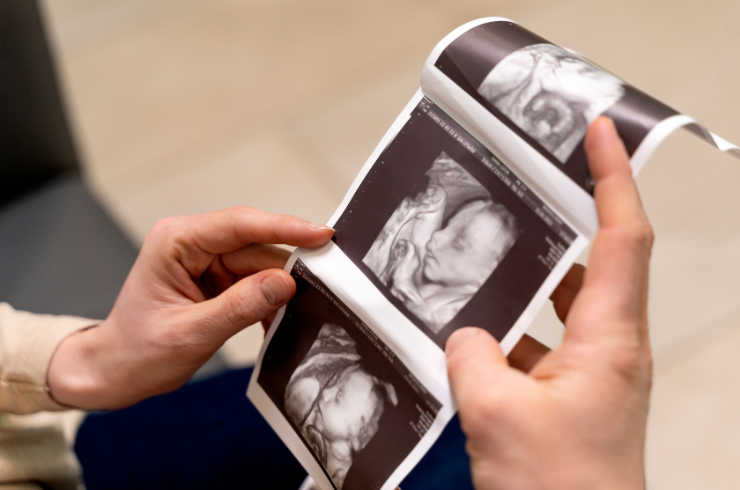

Every Scan Matters

Each scan tells a story. We listen, detect, and guide with precision and care.